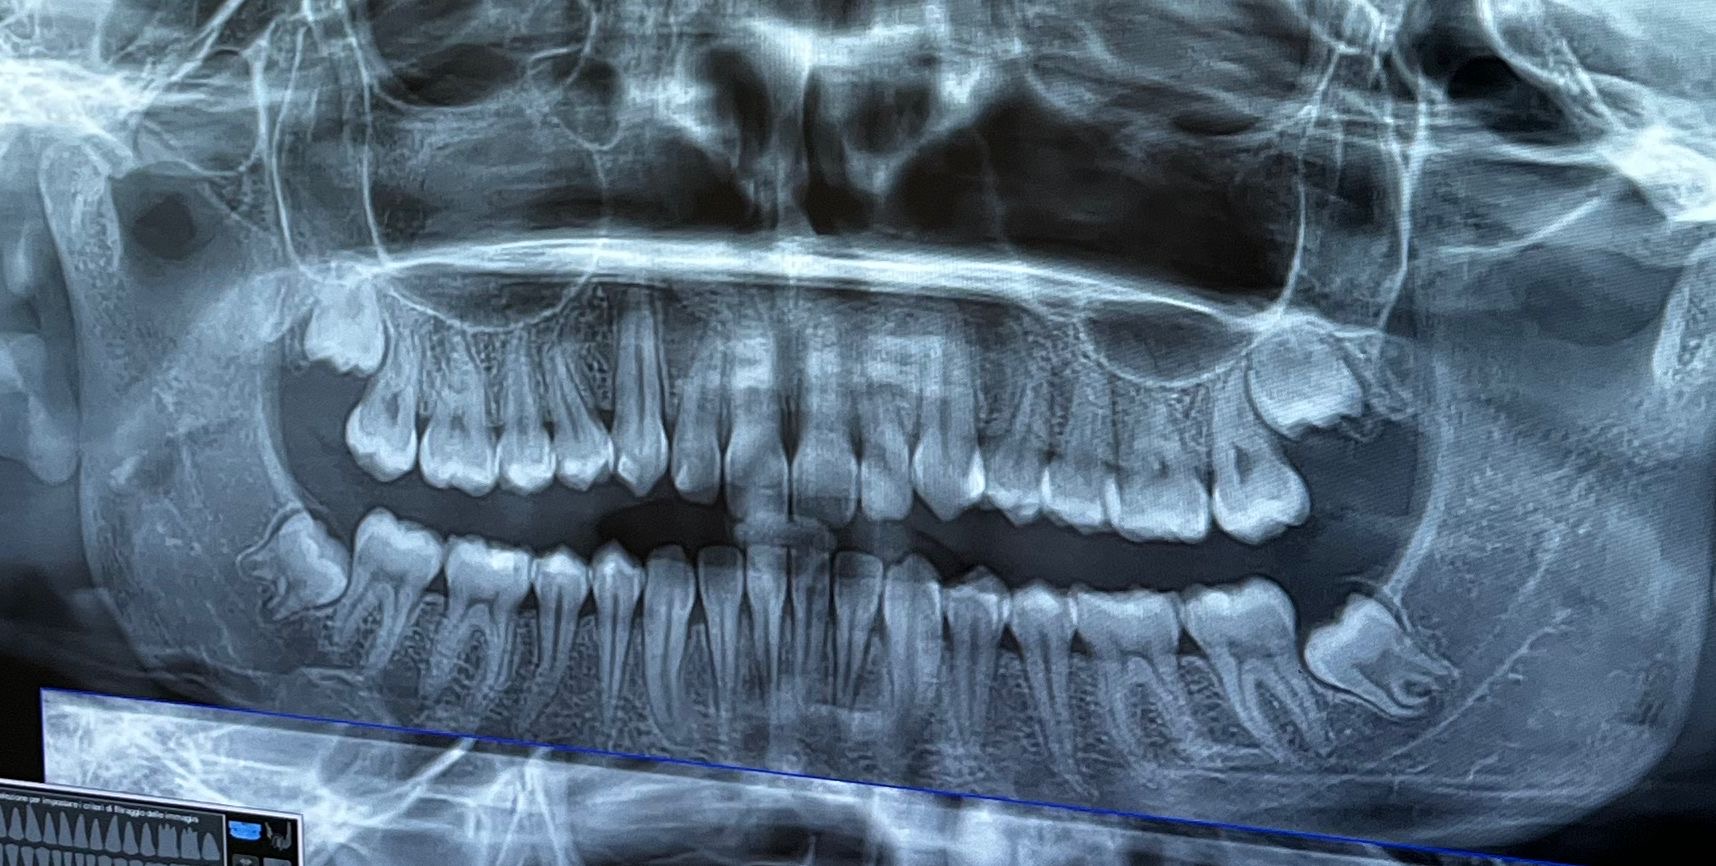

Buonasera Dottore, vorrei un parere chirurgico basato sulla mia ortopanoramica. Mi è stata proposta l'estrazione dei denti del giudizio inferiori (inclusi) a scopo preventivo. Attualmente questi non mi danno alcun problema. Vorrei sapere se, guardando la lastra, ritiene che il rischio di danneggiare i molari vicini o di carie/ infezioni giustifichi l'intervento ora, o se è possibile un monitoraggio nel tempo. Grazie mille in anticipo

Gli ottavi inferiori chiaramente non hanno spazio e a 19 anni non c'è più altra crescita.. Io consiglio sicuramente la estrazione precoce, cioè prima che erompano, per evitare le possibili varie complicazioni.. Uno dei due ha radici molto piccole (a destra se la rx è "montata" bene). Quello di sinistra invece sembra avere qualche rapporto con il canale del nervo: va approfondito con una cone beam, tac odontoiatrica, che ci svelerà la situazione..